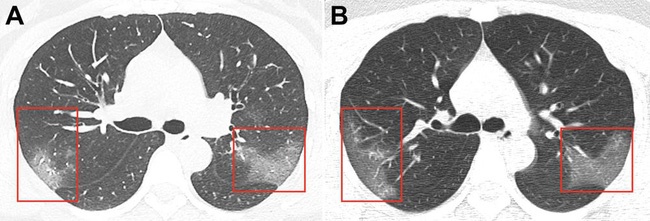

Trong một nghiên cứu được công bố trên tạp chí Radiology tối qua, một nhóm các nhà nghiên cứu tại Bệnh viện đầu tiên của Đại học Lan Châu đã chia sẻ hình ảnh 2 tia chụp X-quang phổi và ngực của người phụ nữ này. Các bản quét cho thấy các mảng trắng ở góc dưới phổi của cô cho thấy hình ảnh "tổn thương kính mờ".

Tuy nhiên, trong trường hợp này, các nhà nghiên cứu còn nhận thấy "tổn thương kính mờ" kéo dài ra ngoài rìa phổi. Đây thực sự là điều bất thường. Lakhani nói: "Điều này chỉ xuất hiện với hội chứng hô hấp cấp tính nặng (SARS) và hội chứng hô hấp Trung Đông (MERS)". Cả SARS và MERS cũng là coronavirus. Chúng là nguyên nhân khiến 8.000 trường hợp mắc bệnh và 774 trường hợp tử vong từ tháng 11/2002 đến tháng 7/2003 tại Trung Quốc. Lakhani cho biết, khi quét các loại virus này, ông nhận thấy "rất nhiều sự tương đồng" với hình ảnh X-quang từ bệnh nhân 33 tuổi.